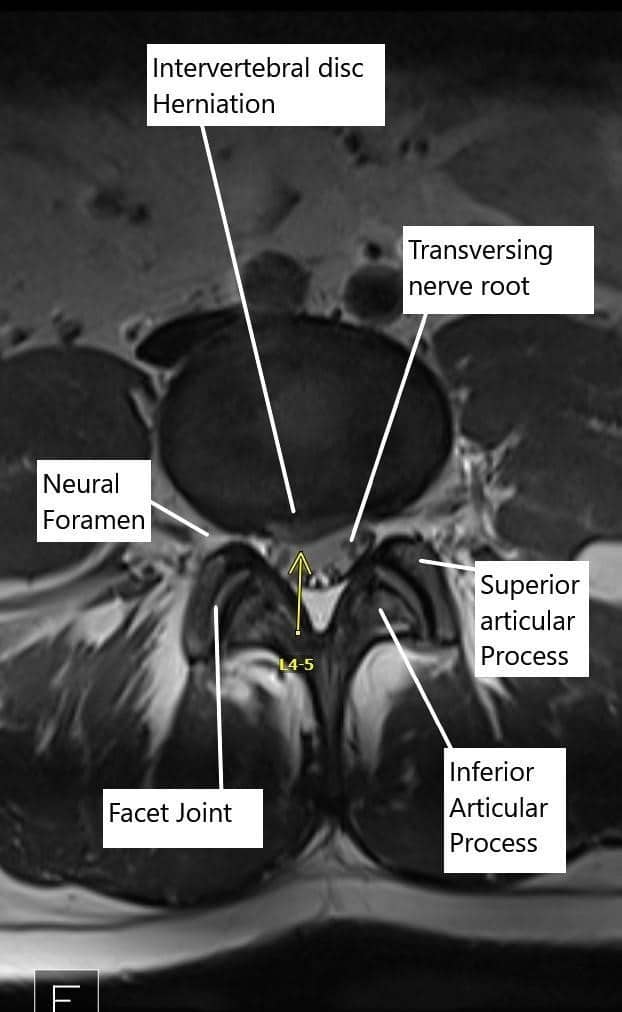

Otros síntomas pueden incluir entumecimiento, sensación de hormigueo, debilidad muscular y cambios en los reflejos. La ciática se considera un síntoma más que un diagnóstico específico, siendo la hernia discal lumbar y la estenosis del canal lumbar o foraminal las causas subyacentes comunes.

Raramente, tumores, quistes u otros factores extraespinales también pueden provocar ciática. Se cree que la inflamación resultante de la irritación o compresión de la raíz nerviosa afectada por los tejidos circundantes es la causa principal de los síntomas.

La ciática se caracteriza típicamente por un dolor que se irradia desde la parte baja de la espalda hacia abajo, pasando por la zona de los glúteos y llegando a una pierna, siguiendo el recorrido del nervio ciático. El dolor suele ser agudo o ardiente y puede ir acompañado de hormigueo, entumecimiento o debilidad muscular. Un profesional sanitario puede diagnosticar la ciática mediante un examen físico y estudios de imagen, como resonancias magnéticas o tomografías computarizadas, para identificar la causa subyacente.